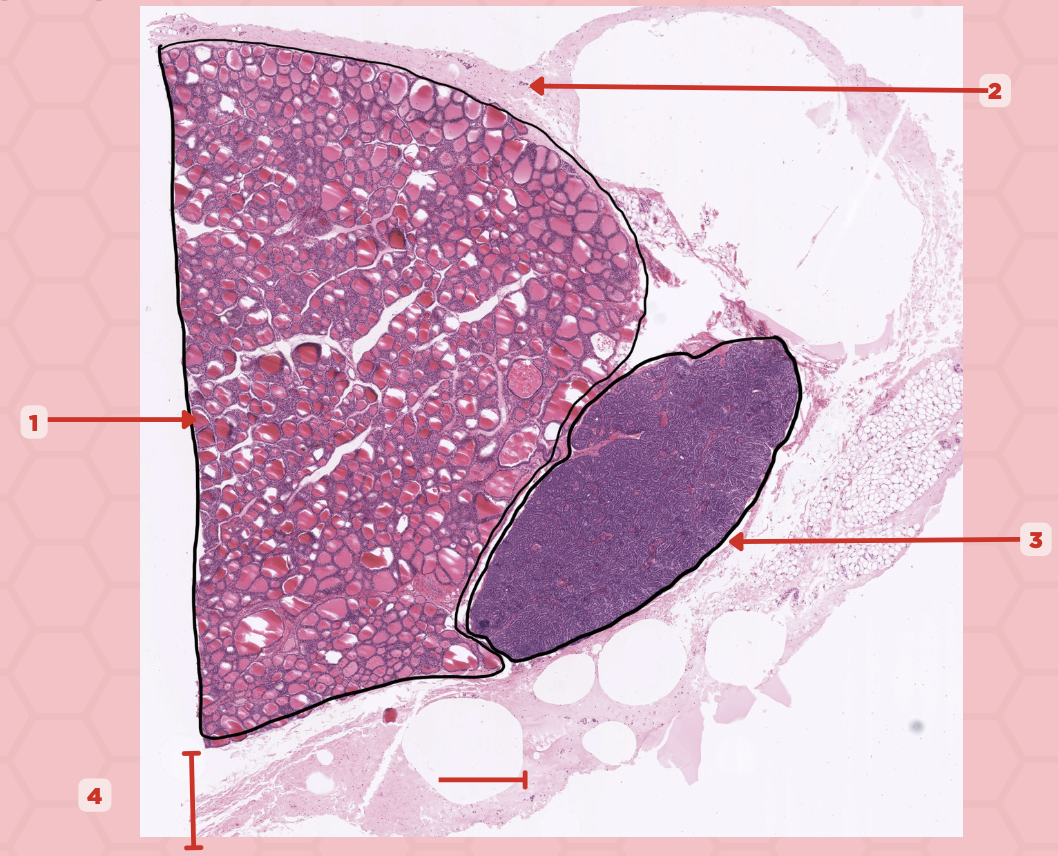

Thyroid

Identify the specimen.

Lobules

Identify the structure labeled as 1.

Follicles

Identify the structure labeled as 2.